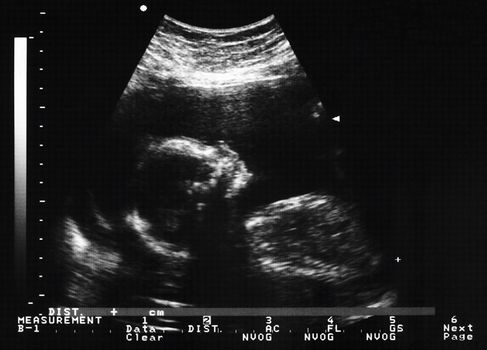

Anomaly scans can diagnose serious conditions and fatal fetal abnormalities which allow health professionals to help manage medical conditions for both mother and baby.

In most OECD countries anomaly scans are routinely offered to expectant mothers, however, in Ireland only five of the 19 maternity hospitals automatically provide them all expectant mums.